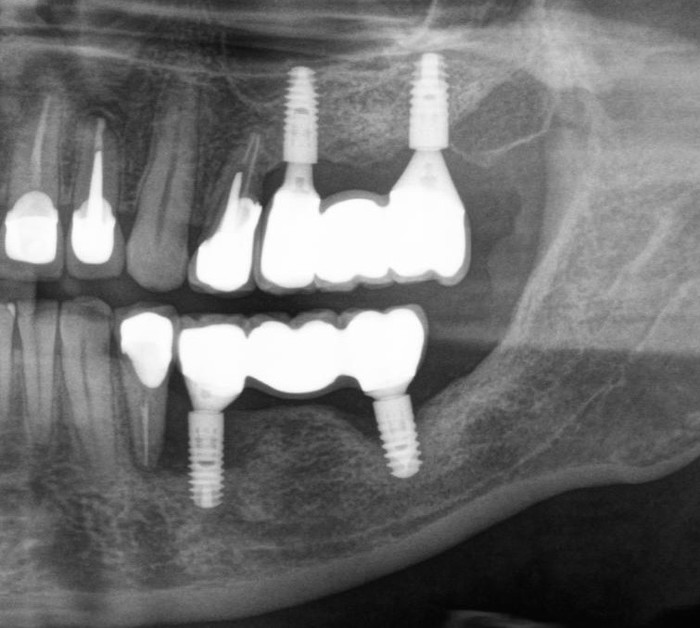

Ниже, на панорамном снимке зубов, мы наблюдаем критичную убыль костной ткани вокруг имплантатов на верхней челюсти.

Оранжевая пунктирная линия - было,

красная - стало.